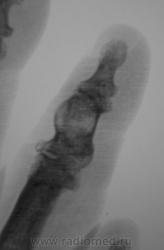

"Пальчик"...

Аневризматическая костная киста. Жалобы есть?

Энхондрома

Туберкулёзный остит средней фаланги 2 пальца.

В дифф.ряд-spina ventosa tuberculosa.

А вот здесь очень близко к костной кисте. Увеличение объема (вздутие), тонкий ободок (стенка) с четкими контурами, содержимое однородное. Даже дифряд строить не хочется.